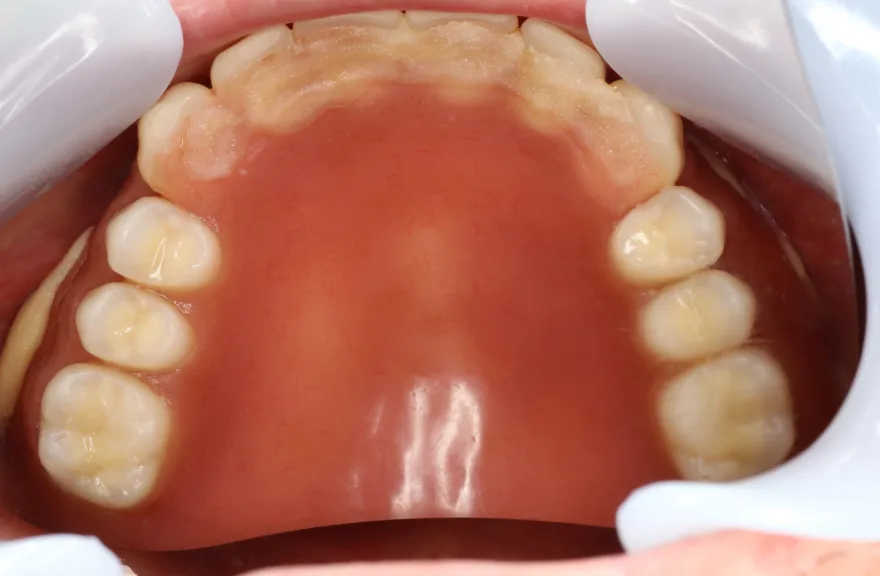

骨格の前後的な差がある方でした。術前のレントゲンより、上下で歯牙の損傷に明らかな差があるのがみてとれます。

今回の症例では、敢えて上顎は総義歯形態をとり、骨格的な前後の差を解消するよう工夫しました。

上顎の残っていた歯も、差し歯としては使えずとも、敢えて根だけ残すことによって組織を温存し、義歯の安定に寄与するよう設計しました。

上顎の総義歯は、馬蹄形という上顎の覆う部分が小さいタイプで作成いたしました。強度に劣るため、割れる可能性があります。